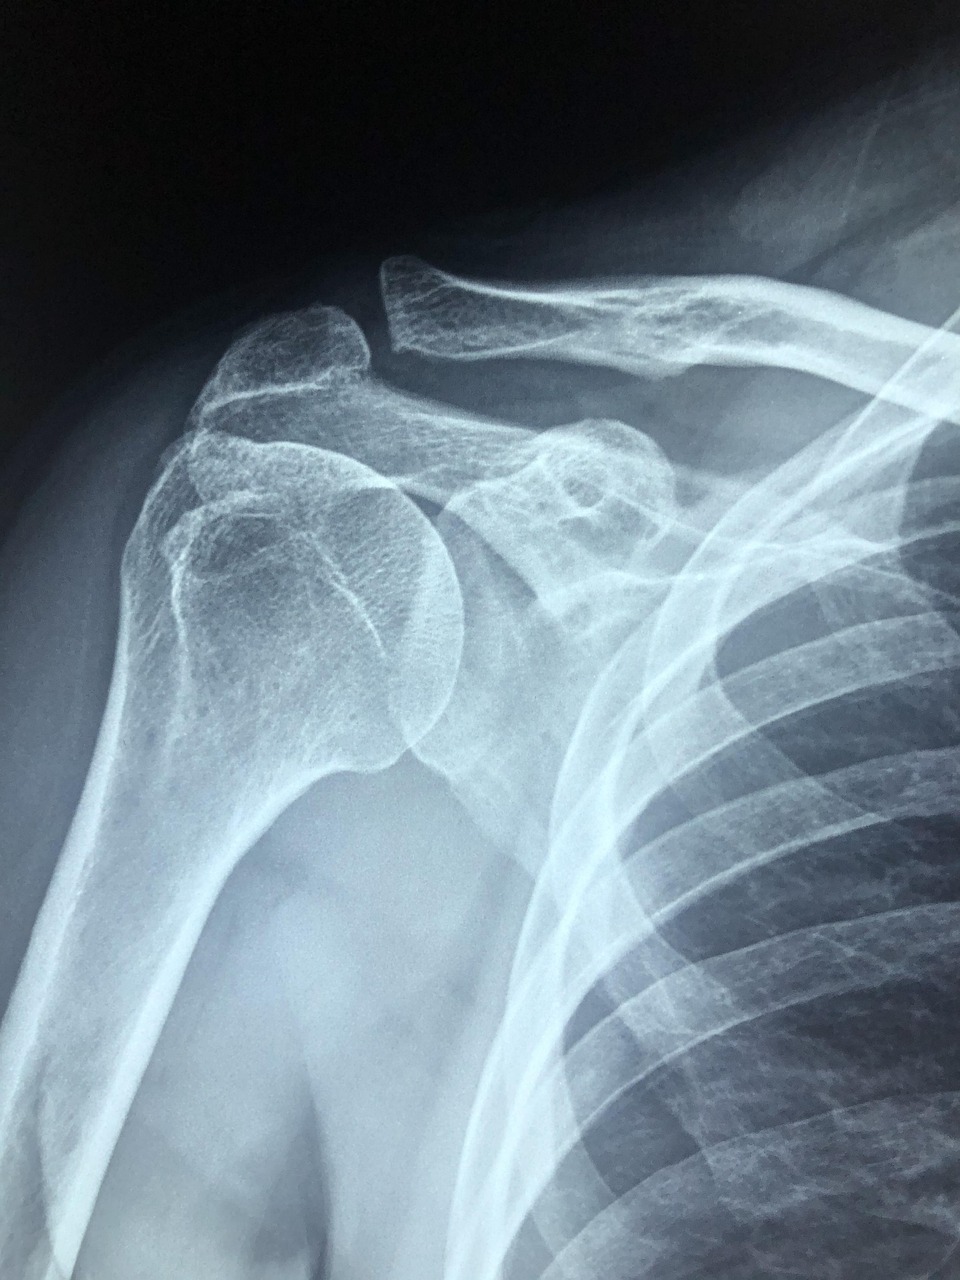

W zależności od wskazań klinicznych, zdjęcia wykonywane są w różnych projekcjach – najczęściej stosuje się projekcję AP (przednio-tylną), osiową, a także tzw. projekcję Y lub transtorakalną (boczną przez klatkę piersiową). Pozwala to na precyzyjną ocenę takich struktur jak kość ramienna, łopatka, obojczyk oraz stawy: barkowy, barkowo-obojczykowy i obojczykowo-mostkowy. Nowoczesne pracownie radiologiczne oferują cyfrowe przesyłanie wyników – obrazy trafiają bezpośrednio do systemu opisowego lekarza radiologa, a pacjent otrzymuje je zazwyczaj na nośniku elektronicznym (CD lub DVD). Takie rozwiązanie umożliwia szybkie przekazanie wyników zarówno do lekarza prowadzącego, jak i do innych specjalistów w razie potrzeby dalszej diagnostyki lub konsultacji.

Wskazaniem do wykonania prześwietlenia barku są przede wszystkim urazy mechaniczne, takie jak złamania, zwichnięcia czy podwichnięcia stawu. RTG umożliwia szybkie potwierdzenie lub wykluczenie uszkodzeń kostnych oraz ocenę ewentualnych powikłań pourazowych. Badanie jest również zalecane w przypadku przewlekłego bólu barku, ograniczenia zakresu ruchomości czy sztywności stawu, które mogą sugerować rozwój zmian zwyrodnieniowych, zapalnych lub reumatoidalnych. W praktyce klinicznej często wykorzystuje się je także do monitorowania procesu leczenia i kontroli po przebytych urazach.

Interpretacja wyniku prześwietlenia barku opiera się na analizie charakterystycznych zmian widocznych w strukturach kostno-stawowych. W opisach radiologicznych często pojawiają się określenia takie jak zmiany zwyrodnieniowe, które mogą być opisane jako początkowe, stopniowe lub zaawansowane. Oznaczają one procesy degeneracyjne prowadzące do utraty chrząstki stawowej i powstawania osteofitów, co przekłada się na ból oraz ograniczenie ruchomości. Innym często spotykanym pojęciem jest PHS (periarthritis humeroscapularis), czyli zespół bolesnego barku – termin ten obejmuje grupę objawów związanych z zapaleniem, uszkodzeniem ścięgien lub kaletek okołostawowych, a także zmianami w obrębie stawu barkowo-obojczykowego.

Wynik badania RTG może również zawierać informacje o cechach zapalenia stawu, takich jak obrzęk tkanek miękkich czy zwężenie szpary stawowej, a także o obecności uszkodzeń ścięgien lub innych struktur miękkotkankowych. Radiolog ocenia także stan stawu barkowo-obojczykowego – jego deformacje, zwapnienia czy ślady przebytych urazów mogą mieć istotne znaczenie dla dalszego postępowania terapeutycznego. W zależności od wykrytych nieprawidłowości lekarz prowadzący może zdecydować o konieczności rozszerzenia diagnostyki (np. o rezonans magnetyczny) lub wdrożeniu odpowiedniego leczenia zachowawczego bądź operacyjnego.

• Zwężenie szpary stawowej na zdjęciu RTG może sugerować rozwijającą się chorobę zwyrodnieniową lub przewlekłe przeciążenia.

• Zwapnienia w obrębie tkanek miękkich są typowe dla przewlekłych stanów zapalnych i mogą wskazywać na tzw. wapniejące zapalenie ścięgien.

• Nierówność powierzchni kostnych oraz obecność osteofitów to objawy postępujących zmian degeneracyjnych.

• Złamania i przemieszczenia kości są jednoznacznym wskazaniem do pilnej interwencji ortopedycznej.

• Zmiany destrukcyjne lub ubytki kostne mogą być sygnałem poważniejszych schorzeń, takich jak martwica kości czy proces nowotworowy.

Prawidłowa interpretacja opisu radiologicznego pozwala nie tylko na rozpoznanie przyczyny dolegliwości pacjenta, ale również na ocenę stopnia zaawansowania procesu chorobowego oraz wybór optymalnej ścieżki leczenia. W razie wątpliwości diagnostycznych możliwe jest skierowanie pacjenta na dodatkowe badania obrazowe, które umożliwią dokładniejszą ocenę tkanek miękkich i struktur okołostawowych barku.